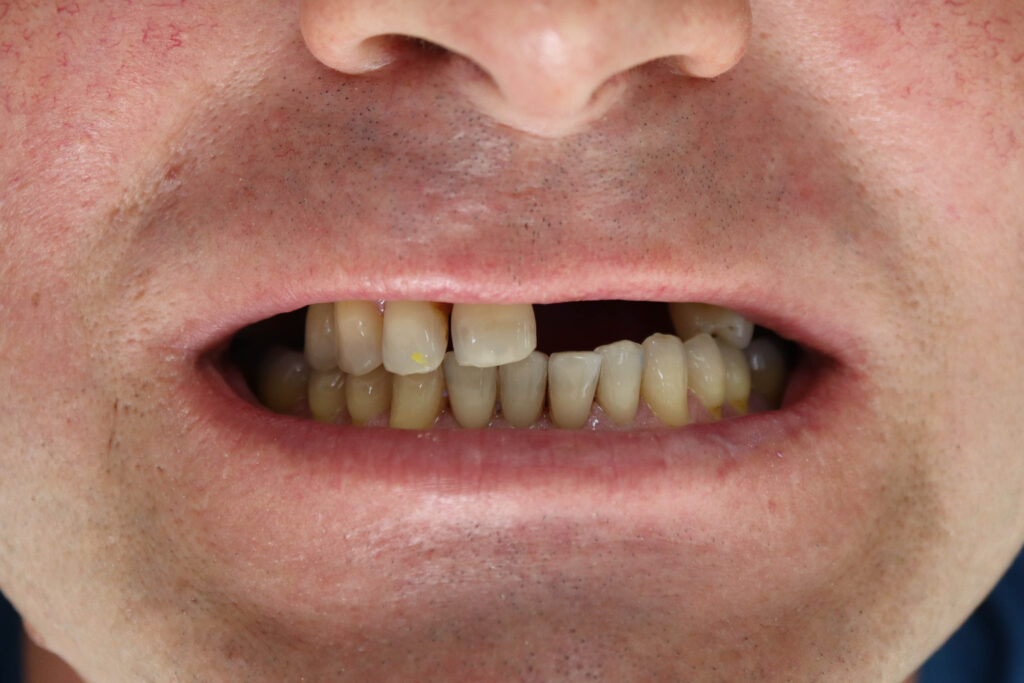

Ситуация до лечения

пациент до имплантации